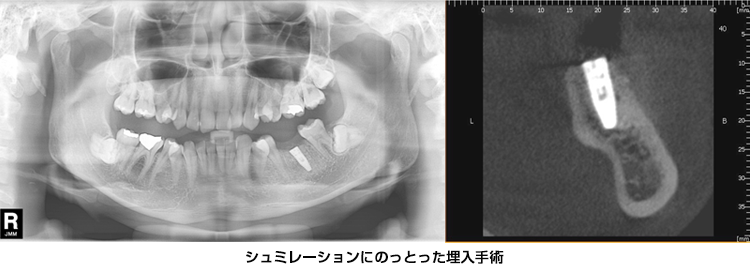

【インプラントの治療事例】

下顎のインプラント

左下の奥はレントゲンでは骨は充分の長さがありそうです(赤枠)。下顎の場合、下顎管(神経、血管の管)までの距離、骨幅の診断がポイントになります。

下顎骨は傾斜している場合が多く、レントゲンでは診断不可能です。

CT断層撮影では下顎管までの距離は19㎜、インプラント治療には十分な長さです。しかし、骨の断面は傾斜してえぐれているのが解ります。骨を突き抜けると大変です

CT上でシュミレーションして骨を突き破らないインプラントのサイズを決定します。

CT断層撮影で3次元的な骨の状態、血管の位置を術前に診断できます。それにより、安心、安全に治療を行えます。